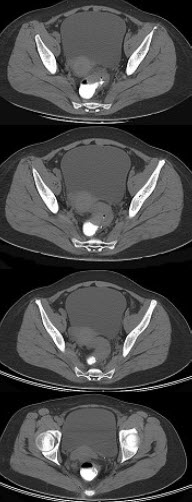

男,67岁,排便习惯改变,血便三个月入院,CT检查如图所示,下列说法错误的是( )

A:直肠肠腔局限性增厚

B:其表面欠光整,边界欠清晰

C:可做直肠指检及活检以确定病变性质

D:此为直肠息肉

E:此为直肠癌